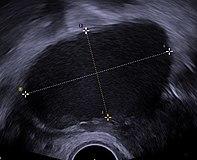

- Transvaginal ultrasonography showing a 67 x 40 mm endometrioma, with a somewhat grainy content.

Ovarian cysts are usually diagnosed by ultrasound, CT scan, or MRI, and correlated with clinical presentation and endocrinologic tests as appropriate.[10]

Ultrasound

Follow-up imaging in women of reproductive age for incidentally discovered simple cysts on ultrasound is not needed until 5 cm, as these are usually normal ovarian follicles. Simple cysts 5 to 7 cm in premenopausal females should be followed yearly. Simple cysts larger than 7 cm require further imaging with MRI or surgical assessment. Because they are large, they cannot be reliably assessed by ultrasound alone; it can be difficult to see posterior wall soft tissue nodularity or thickened septation due to limited ultrasound beam penetrance at this size and depth. For the corpus luteum, a dominant ovulating follicle that typically appears as a cyst with circumferentially thickened walls and crenulated inner margins, follow up is not needed if the cyst is less than 3 cm in diameter. In postmenopausal patients, any simple cyst greater than 1 cm but less than 7 cm needs yearly follow-up, while those greater than 7 cm need MRI or surgical evaluation, similar to reproductive age females.[11]